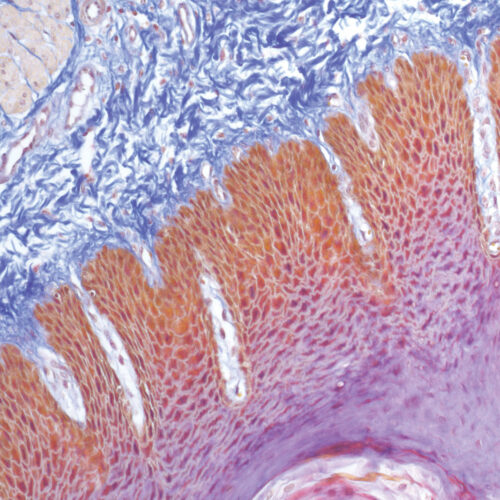

Azan Trichrome kit

Five-reagent kit for connective tissue staining according to Mallory. Used for visualization of muscle fibers, collagen, glial cells, glomerular cells and erythrocytes.